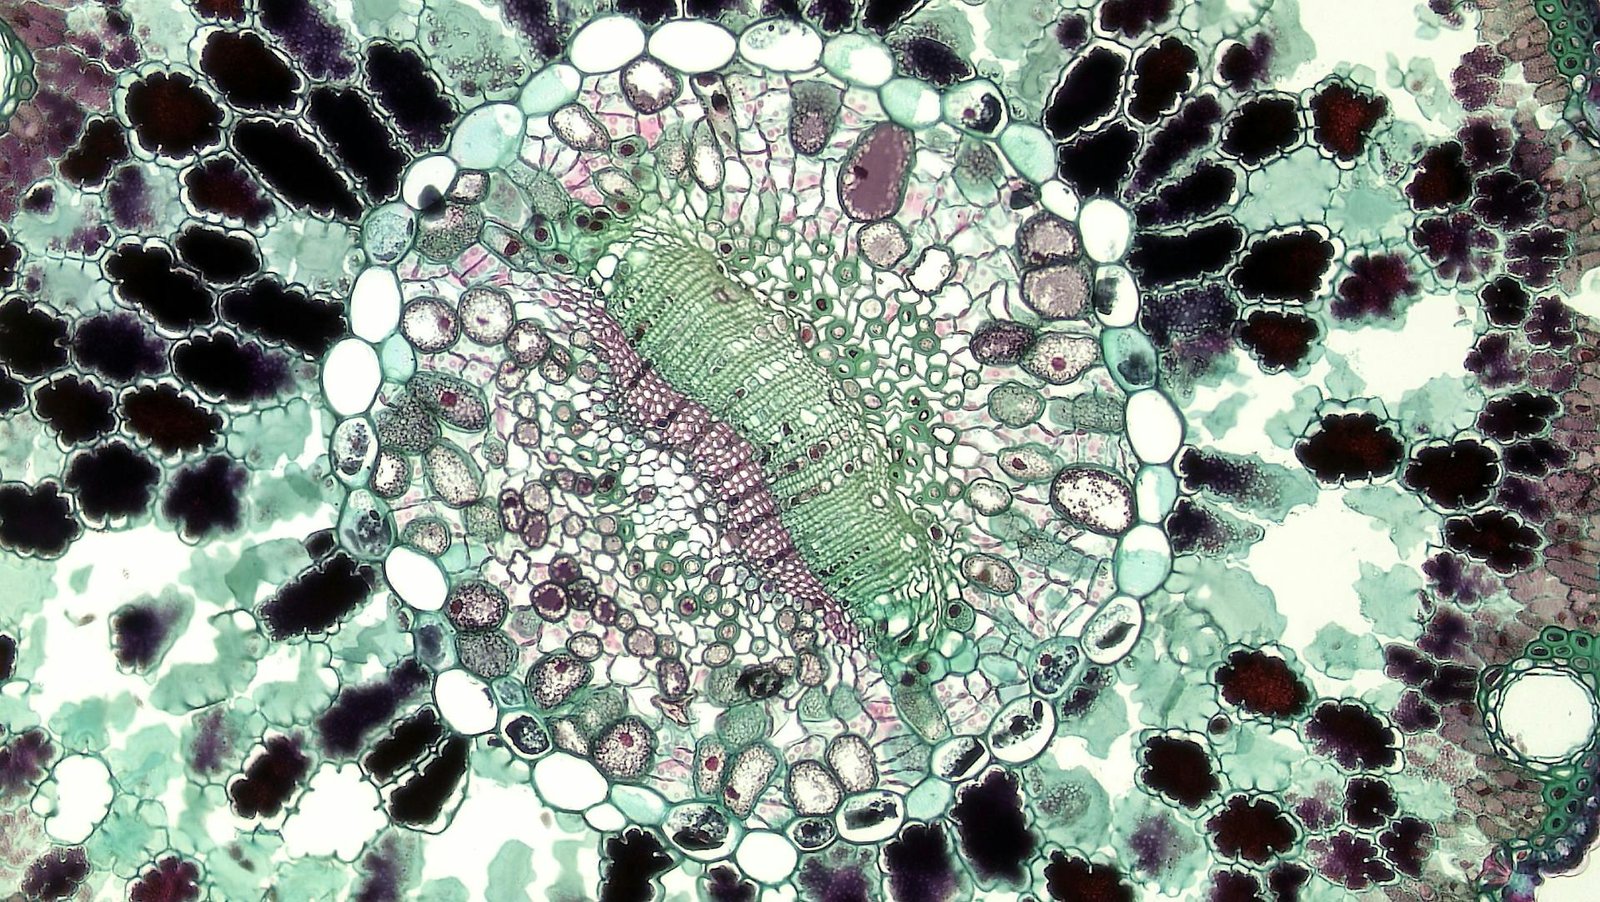

Mesenchymal stem cells (MSCs) are a type of multipotent adult stem cell first discovered in bone marrow but also present in adipose tissue, umbilical cord, placenta, dental pulp, and other sources.

- MSCs can self-renew and differentiate into osteoblasts (bone cells), chondrocytes (cartilage cells), and adipocytes (fat cells).

- They express specific surface markers (positive for CD73, CD90, CD105; negative for CD34, CD45).

- They can be expanded in culture and retain therapeutic properties. In simple language, it means that we can extract few MSC cells from certain tissues like fat cells (most readily accessible source in patients), and then multiply them in labs to increase their quantity to manage health conditions.

MSCs contribute to tissue repair not only by differentiating into local cells but also through paracrine effects, which means that they release bioactive molecules (cytokines, growth factors, and exosomes) that:

- Reduce inflammation

- Suppress immune responses

- Promote angiogenesis (formation of new blood vessels)

- Encourage native cell regeneration